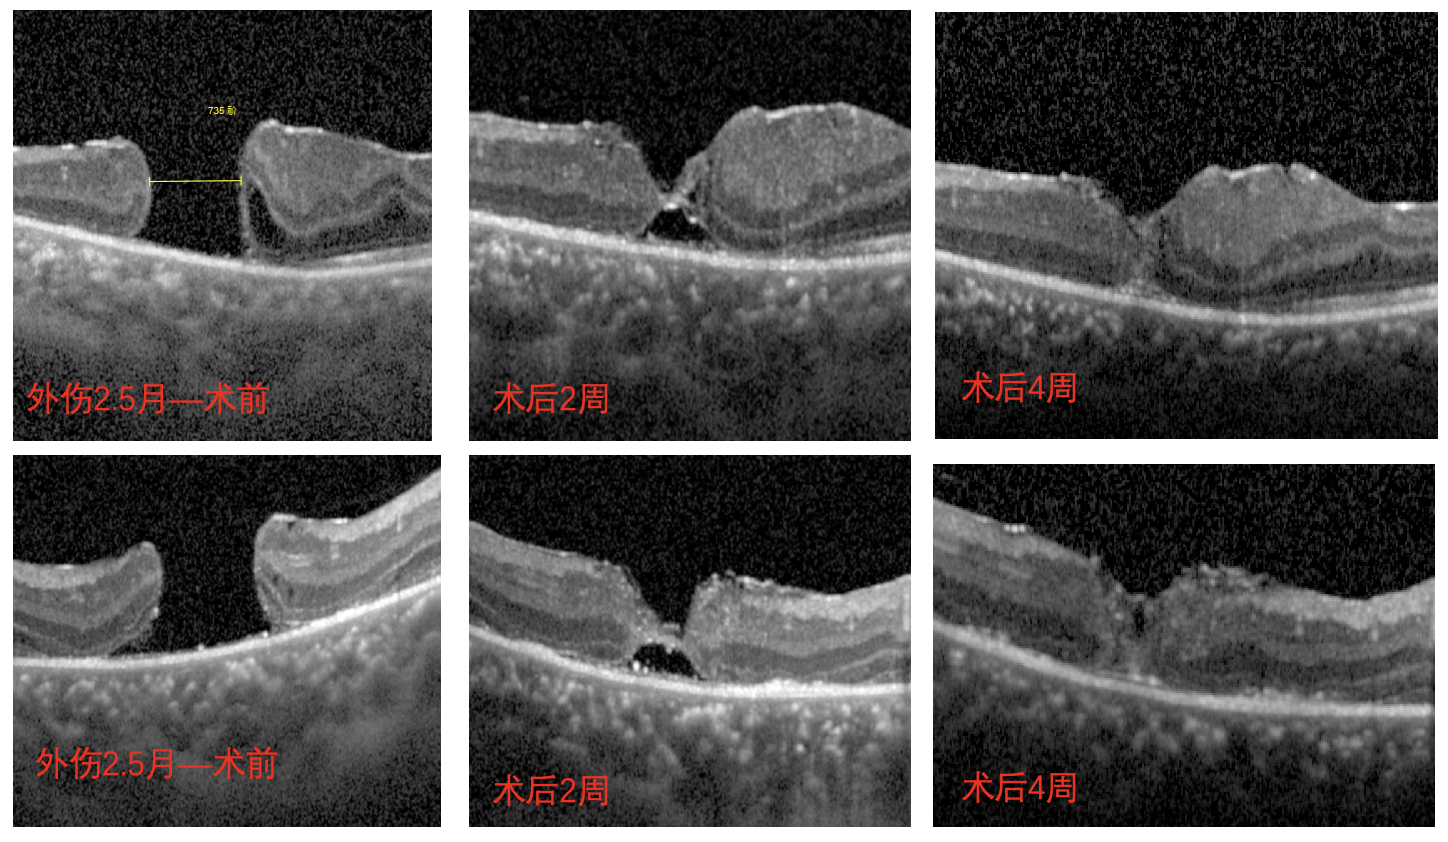

外傷黃斑裂孔術(shù)后演變成難治性黃斑裂孔,小孩千里尋醫(yī)求診挽救 “視” 界

【文章導(dǎo)讀】一次意外,南南(化名)眼睛受傷致眼底黃斑裂孔。此后,家長開始帶著他踏上了漫長的求醫(yī)之路 1. 手術(shù)的困境:漫長的煎熬與未愈的裂孔 去年,南南因眼睛不慎受傷致黃斑裂孔,在

去年,南南因眼睛不慎受傷致黃斑裂孔,在保守治療無效后,立即在當(dāng)?shù)蒯t(yī)院接受了手術(shù)治療。手術(shù)采用傳統(tǒng)的黃斑裂孔手術(shù)方式,術(shù)中填充了長效氣體,術(shù)后按照醫(yī)囑,南南需要長期保持面部向下體位(即俯臥位)來幫助恢復(fù)。這對于活潑的南南來說無疑是一種折磨,家長看在眼里,疼在心里。

但術(shù)后一個月復(fù)查時發(fā)現(xiàn),南南的眼底恢復(fù)情況并不好,檢查時還可見黃斑處的裂孔,并且裂孔越來越大,演變成難治性黃斑裂孔。

為了尋求更好的治療效果,南南家長帶著他到省城的眼科醫(yī)院看診,并再次進行手術(shù)治療。術(shù)后,又是漫長的一個月趴睡恢復(fù)期。

只是,這次的治療除了讓南南更加抗拒和難受之外,并沒有給他們帶來驚喜。一個月后的復(fù)查結(jié)果提示:南南傷眼的裂孔依舊并未愈合。

經(jīng)過完善的術(shù)前檢查和評估后,李海波博士后用創(chuàng)新術(shù)式——剝除黃斑裂孔周邊殘余的內(nèi)界膜組織,通過利用黏彈劑固定翻轉(zhuǎn)的內(nèi)界膜瓣為南南進行治療。術(shù)后24小時復(fù)查時,南南黃斑處的裂孔已實現(xiàn)愈合,視力也得到了明顯的改善,現(xiàn)已康復(fù)出院。